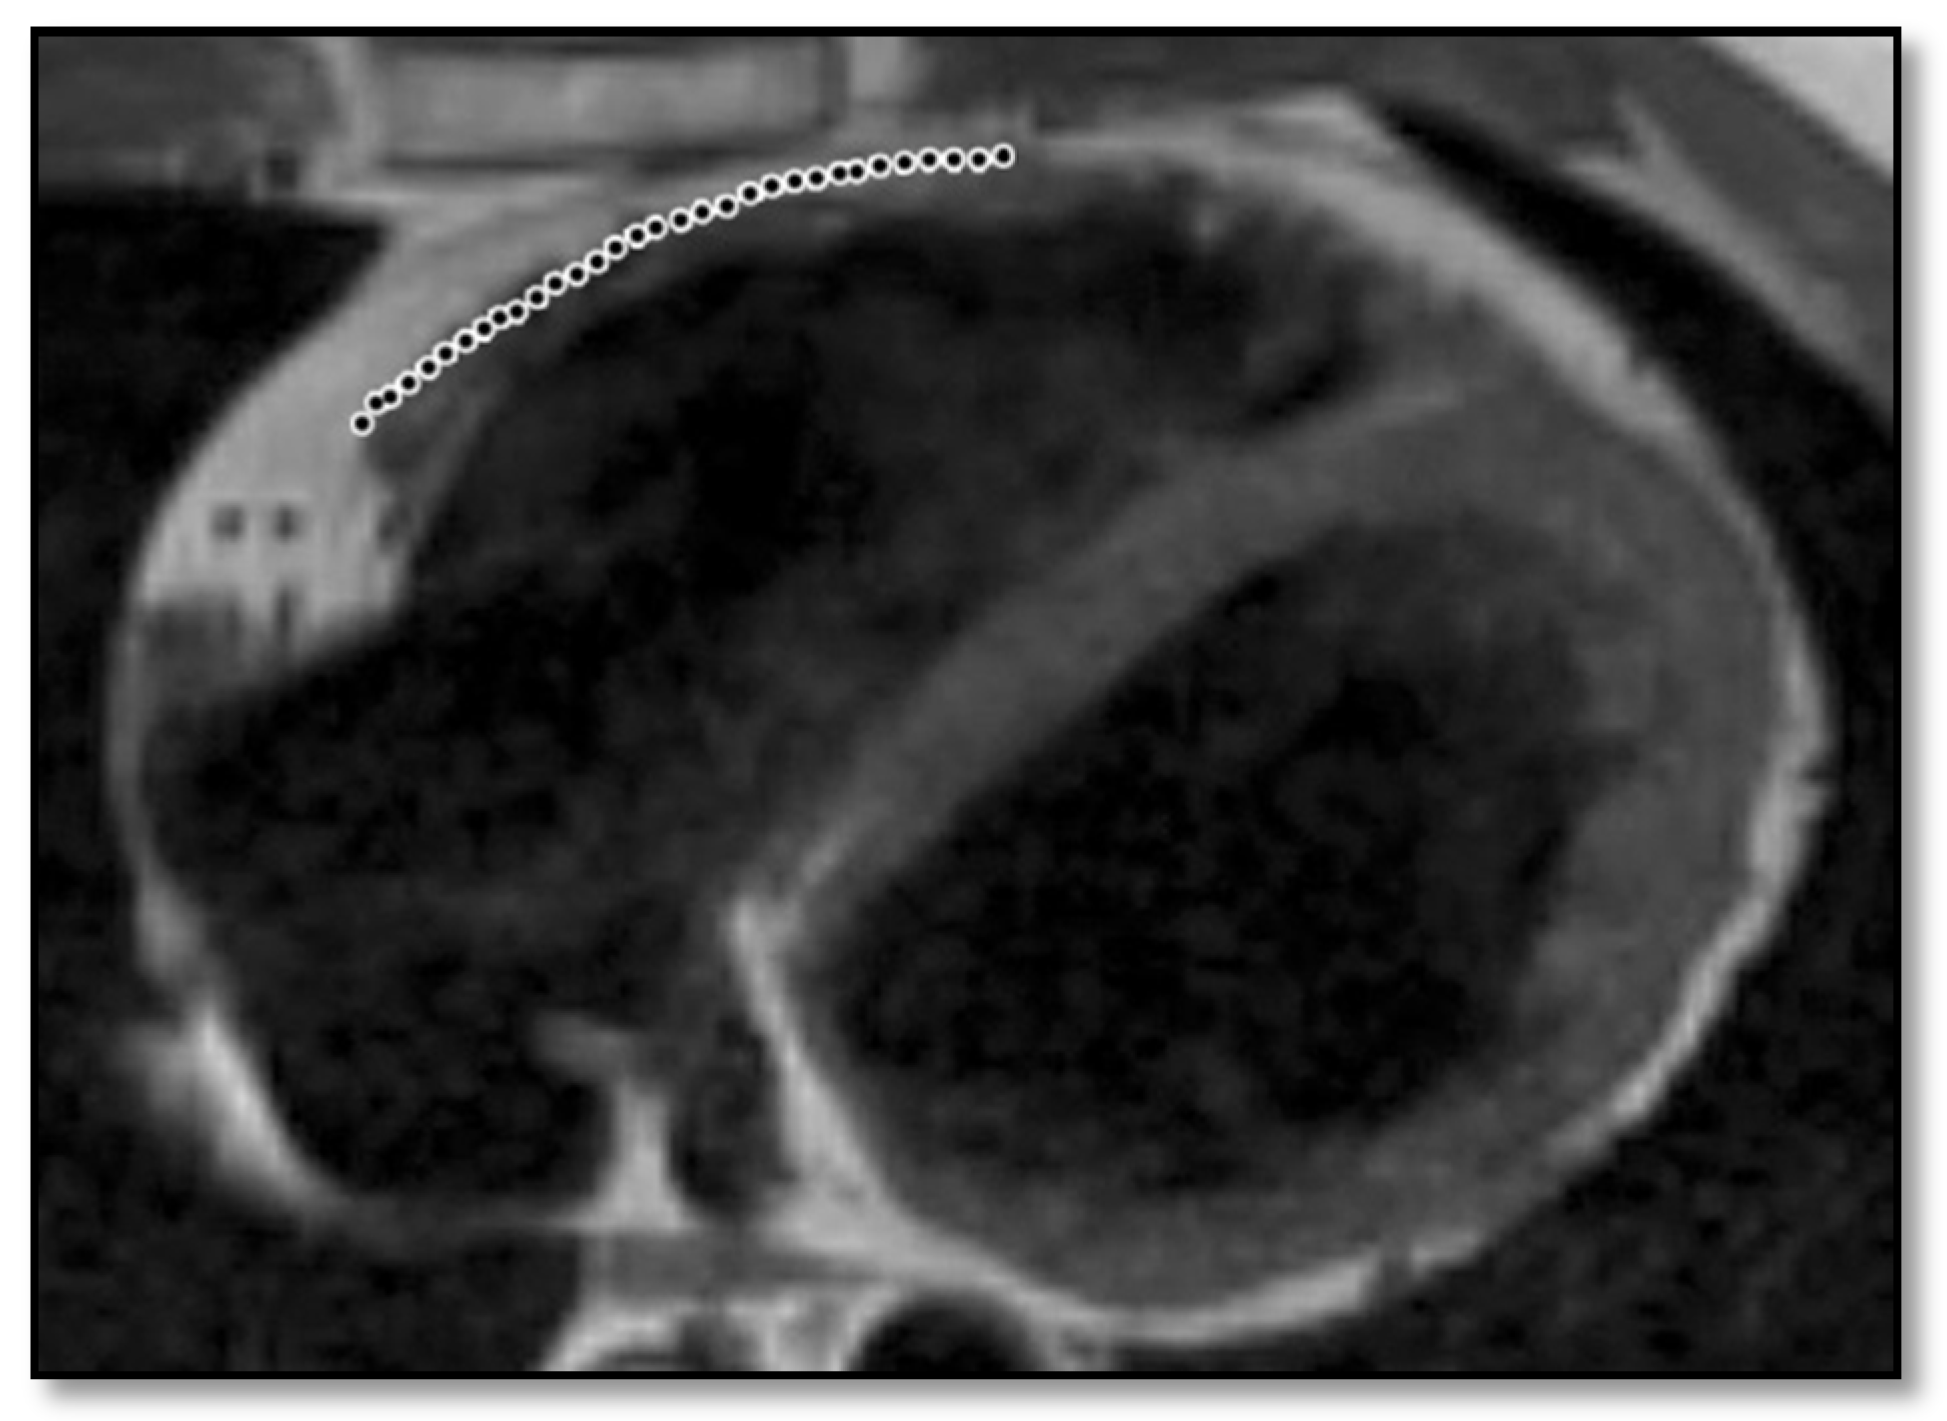

- RV contraction disorders and functional abnormalitiesUnlike the initial diagnostic criteria, the 2010 Revised Task Force Criteria [12] are quantitative rather than qualitative. Three types of changes were included: (1) segmental RV contraction abnormalities, (2) dilation of the RV, and (3) reduction of the RV ejection fraction. It is notable that intramyocardial fat or delayed enhancement are not included in the criteria for differential diagnosis strictly because these changes can be found in healthy people or in other diseases affecting the right ventricle. The association between akinesia/dyskinesia or RV regional contraction asynchrony with RV volume dilation or RV ejection fraction <40% is considered a major criterion for the diagnosis. As mentioned beforehand, the Revised Criteria are quantitative. Therefore, RV dilation is defined as the ratio of RV volume/body surface area > 110 mL/sqm in men or >100 mL/sqm in women. The minor criterion is defined as the presence of akinesia/dyskinesia with decreased ejection fraction of 40 to 45%, contraction abnormalities, or increased RV volume between 100 and 110 mL/sqm in men or 90 and 100 mL/sqm in women. It is worth noting that microaneurysms as well as segmental RV dilatations were removed from the Diagnostic Criteria because they are rather subjective and challenging to evaluate.

- RV dilation is also a key element for the diagnosis of ARVC. It can be segmental or global. Segmental expansion can affect only the RVOT or parts of the RV such as the basal free wall or the middle third of the free wall. It is a diagnostic criterion with high sensitivity and specificity for ARVC (Figure 3). Only the global dilation of RV is considered a diagnostic criterion for ARVC because segmental dilatation is rather difficult to interpret [12,45].